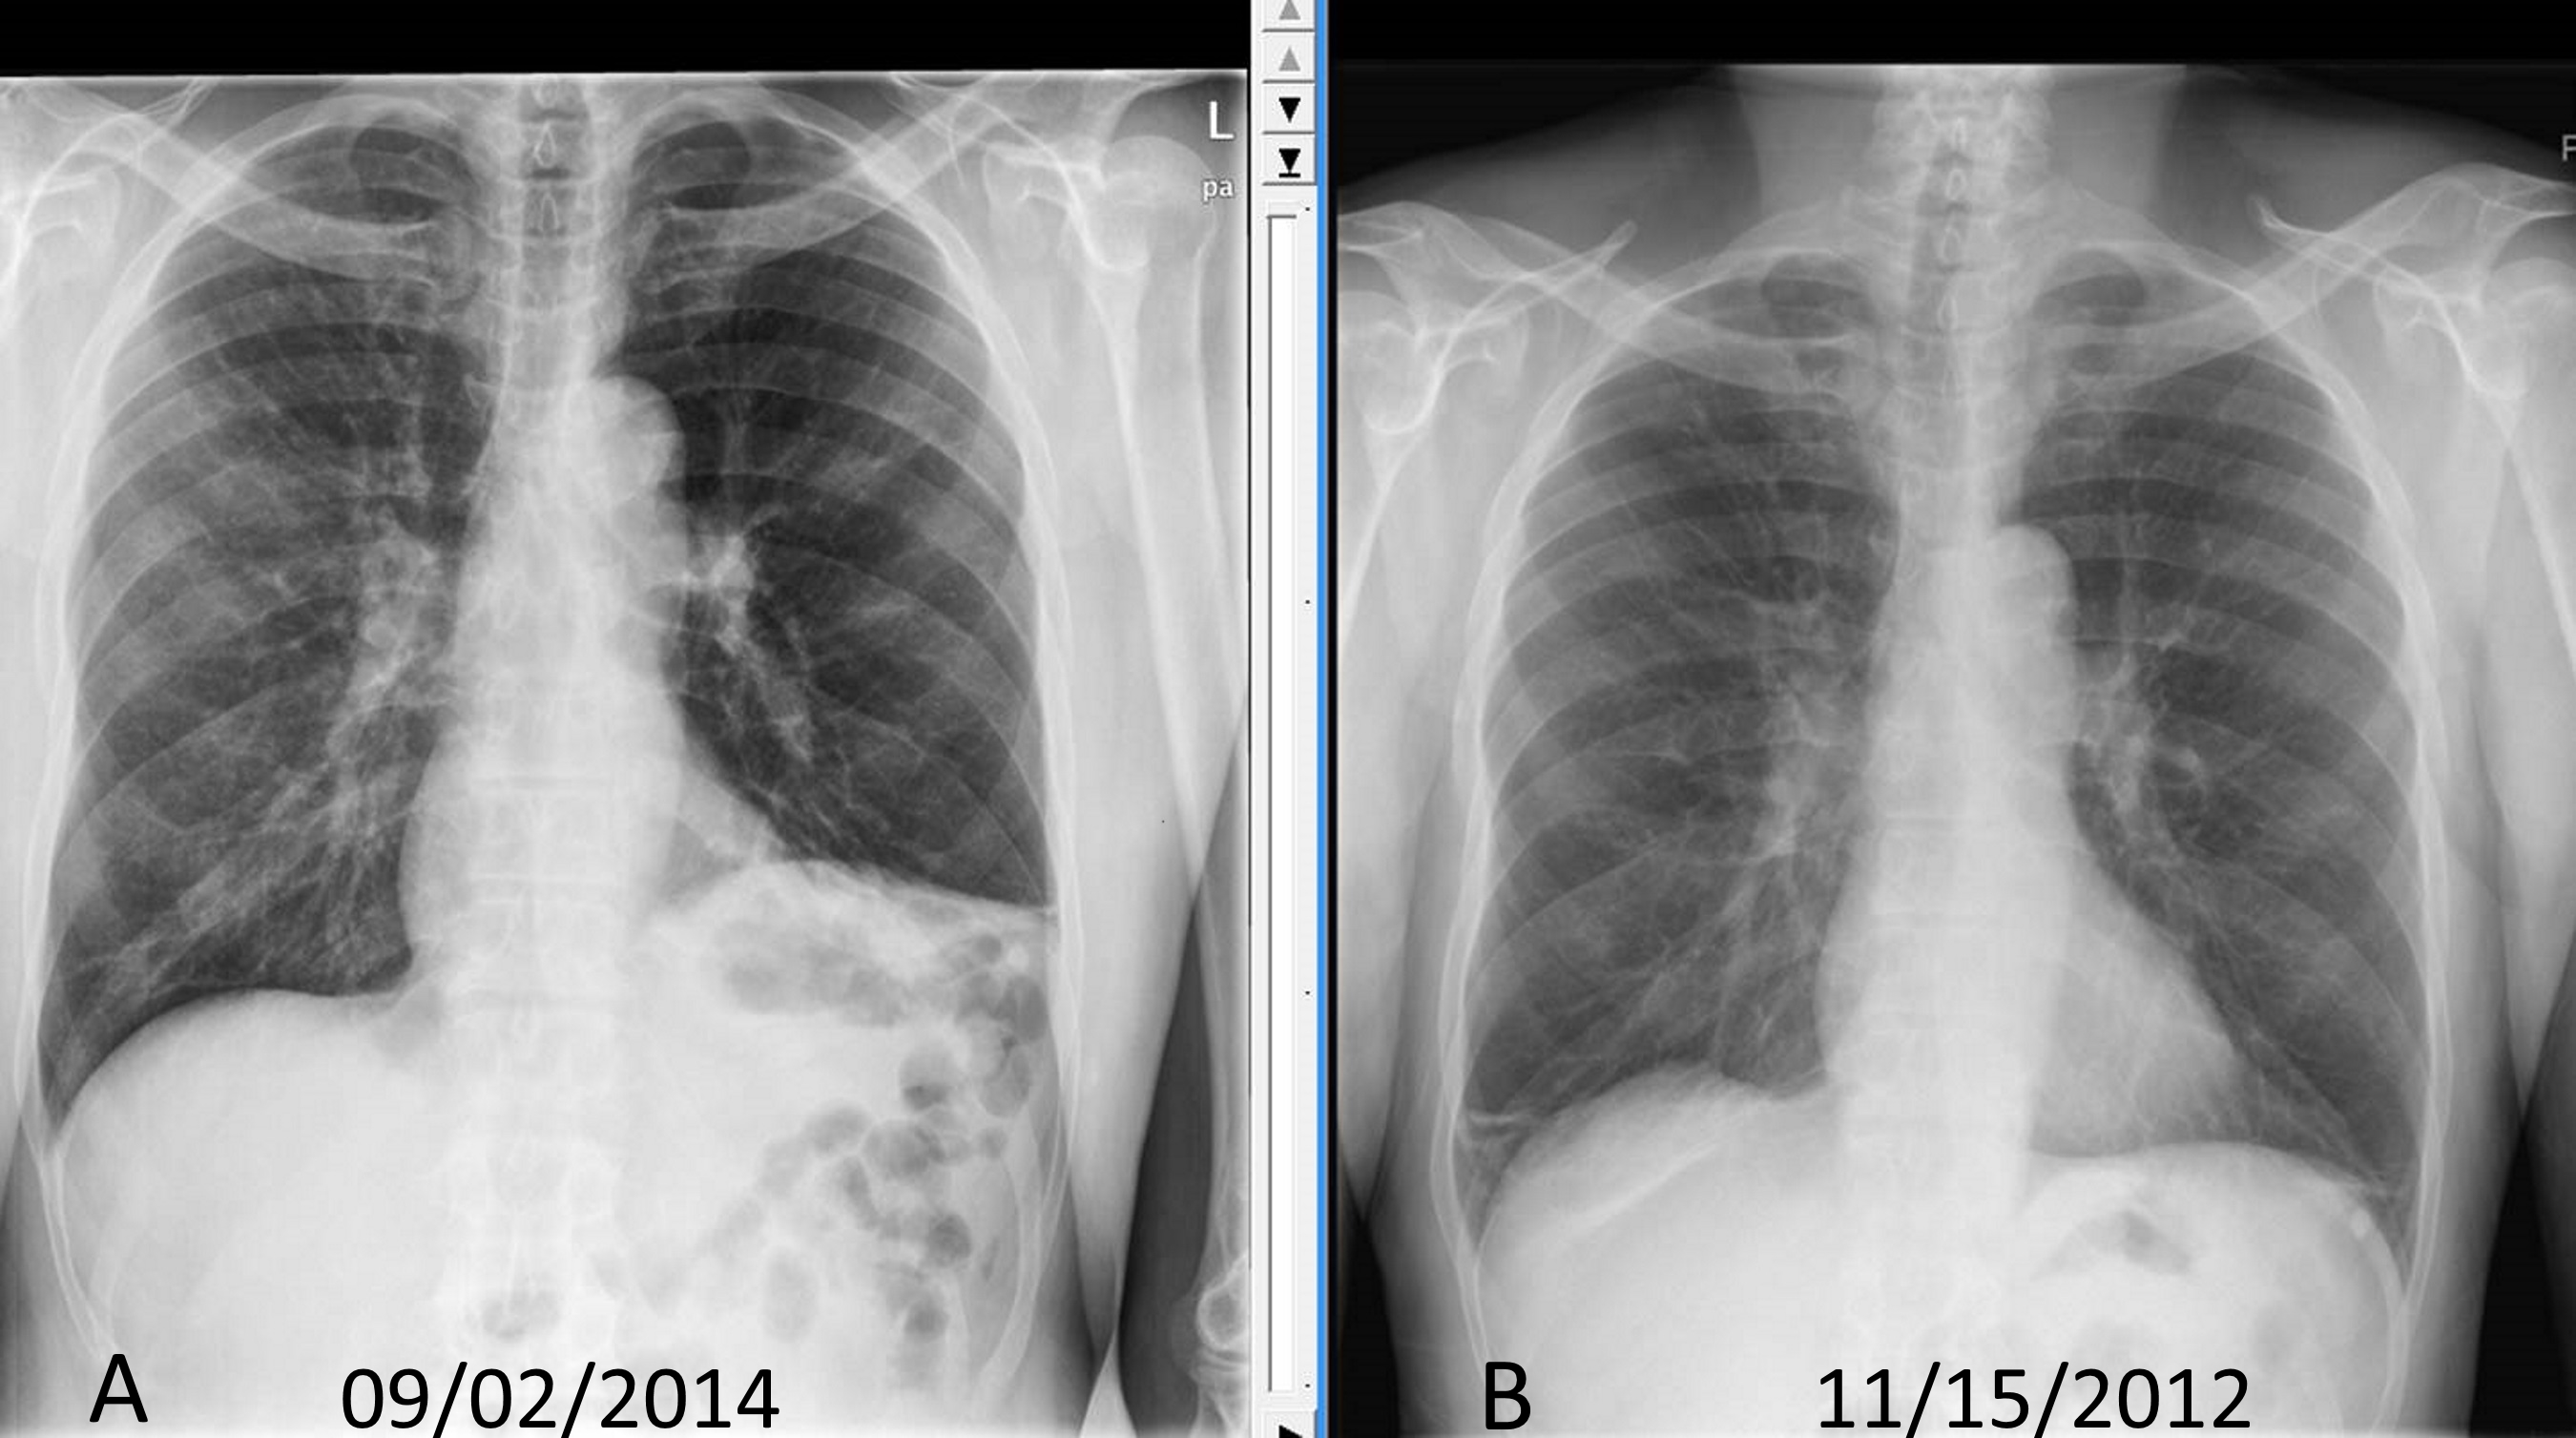

Pneumoperitoneum and subphrenic abscess are two important differential diagnosis of this radiographic sign which can be excluded out when normal plicae circulares or haustral markings of the colon is seen under the right diaphragm. If youre experiencing mild discomfort in your diaphragm take a few minutes to concentrate on deep breathing. Treatment depends on the type of hiatal hernia you have and on your symptoms.

Place one hand on your abdomen and breathe deeply. Reduced number of alveoli air sacs required for normal breathing. In severe cases when there is no simple treatment that can relieve dyspnea your doctor may prescribe morphine. Congenital diaphragmatic hernia CDH. There is usually a long history of heavy smoking. Shortness of breath may be accompanied by wheezing. Diaphragmatic dysfunction caused by transverse myelitis or leukemic infiltration of the cervical spinal cord in a patient with leukemia and shortness of breath. To treat phrenic nerve irritation This condition can be managed with a breathing pacemaker which takes over the responsibility of sending messages to the diaphragm. The cause for shortness of breath was thought primarily due to stable angina on tread mill test positive finding but Chilaiditis syndrome should also be considered as a cause for the shortness of breath.